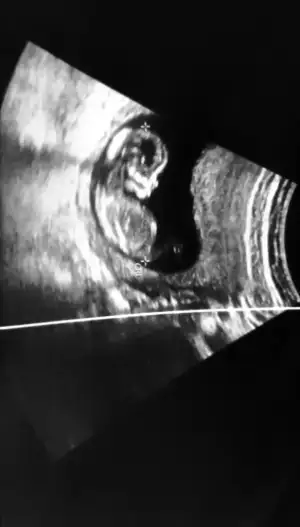

- 5 Mayıs 2020

- 1.603

- 3.306

- 83